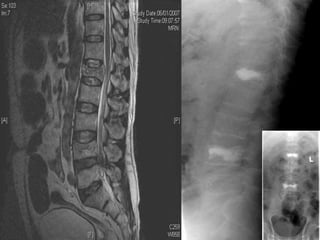

This document discusses maintaining proper posture to prevent back pain and injury. It recommends sitting with neutral spine alignment, either by sitting forward on the chair without back support or leaning back with back support. Certain postures can increase back injury risk factors. The document also mentions biopsy procedures for cancer diagnosis and treatment options for back pain including physical therapy, injections, and surgery, noting minimally invasive surgeries have benefits like better patient outcomes, lower costs, shorter hospital stays and recovery times, and less invasiveness especially for the elderly.